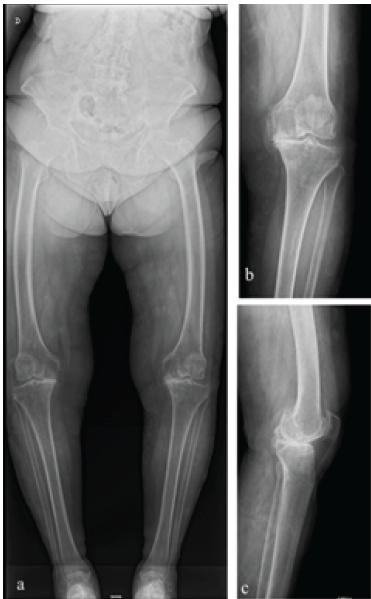

Radiographic evaluation (anteroposterior, lateral, and long-leg standing radiographs) revealed Kellgren–Lawrence Grade IV osteoarthritis with marked anterolateral femoral bowing (Fig. 1a, b, c).

Figure 1: (a) Pre-operative standing long-leg anteroposterior (AP) radiograph showing advanced left knee osteoarthritis with varus deformity and severe anterolateral femoral bowing. (b) Pre-operative standing AP radiograph. (c) Pre-operative standing lateral radiograph.